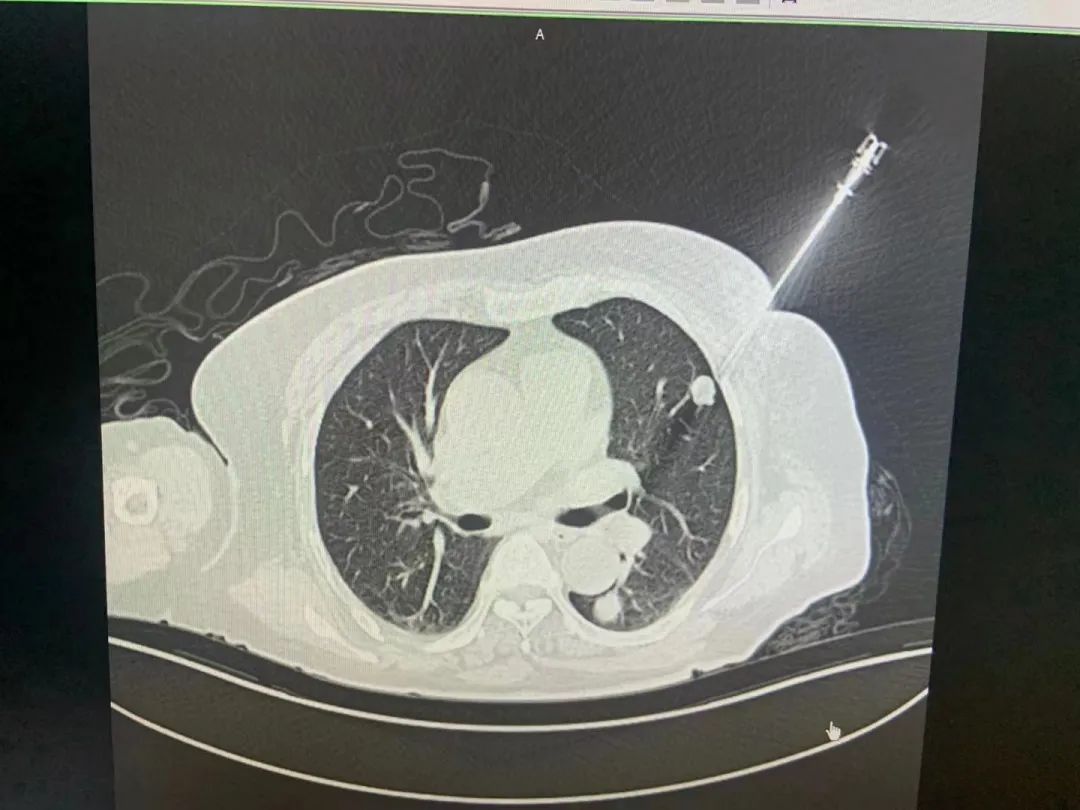

腫瘤穿刺機(jī)器人是睿觸科技成立后生產(chǎn)的第一款產(chǎn)品,如今已經(jīng)在長(zhǎng)三角兩家??迫揍t(yī)院開展臨床試驗(yàn)。這款手術(shù)機(jī)器人不僅將穿刺活檢精度提高了十倍以上,而且將穿刺時(shí)間縮短了數(shù)十倍,極大提高了手術(shù)效率和便捷度,降低了病人的痛苦。

“人體的腫瘤藏在很深的組織里,必須通過醫(yī)學(xué)影像,也就是CT等技術(shù)來查找?!眲忉尩溃凑諅鹘y(tǒng)的操作方法,腫瘤穿刺中手術(shù)機(jī)器人必須借助醫(yī)學(xué)影像來進(jìn)行引導(dǎo),然而這兩者之間其實(shí)是“互相不認(rèn)識(shí)的”關(guān)系?!耙?yàn)镃T和機(jī)器人是各自獨(dú)立的兩套坐標(biāo)系,必須借助光學(xué)傳感器來建立聯(lián)系,但這樣也會(huì)導(dǎo)致精度的損失,成像效果不理想,影響手術(shù)進(jìn)程?!币虼?,睿觸科技將這兩者進(jìn)行了大膽結(jié)合,用劉劍的話說,就是“讓他們互相認(rèn)識(shí)對(duì)方”。

“我們采取了全新的設(shè)計(jì),把人體的三維腫瘤信息實(shí)時(shí)地告訴機(jī)器人,讓機(jī)器人開啟智慧之眼,比如距離有多遠(yuǎn)、角度差了多少度等等,這樣就能引導(dǎo)醫(yī)生來做更精準(zhǔn)的腫瘤治療手術(shù)?!比绱?,在腫瘤早篩領(lǐng)域,這樣一款精確、快速、安全的經(jīng)皮穿刺手術(shù)機(jī)器人,能讓更多腫瘤患者可以早發(fā)現(xiàn)、早診斷、早治療。